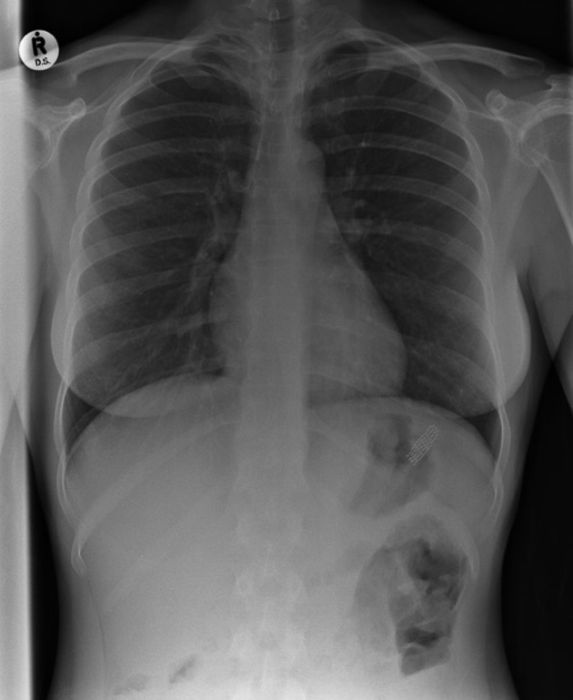

Рентгеновские снимки людей, которые умудрились сами или с чужой помощью разместить внутри своего организма разные посторонние предметы. От вилок и ножей до пуль и бензопилы (!!!). По этическим соображениям обычные снимки таких травм и повреждений выкладывать нельзя, зато рентгеновские можно – на них травмы видны достаточно условно, хоть и очень понятно.